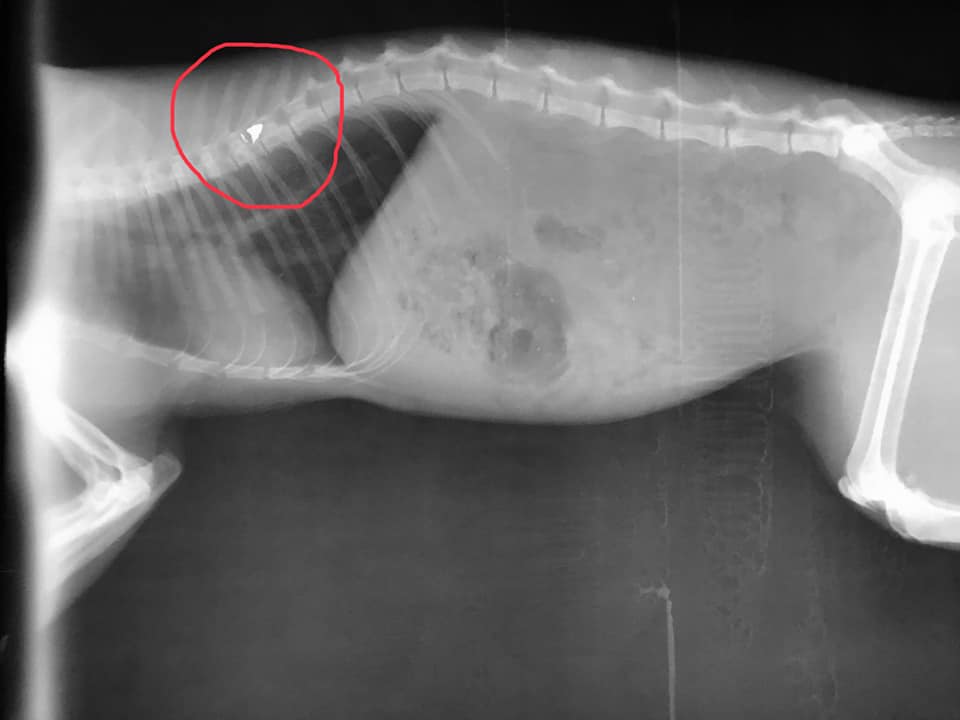

Το σφαιρίδιο στην σπονδυλική στήλη του ζώου.

Η γάτα αρχικά είχε μεταφερθεί στους κτηνιάτρους Μπατίκας Δ. – Μόσχος Γ. αλλά καθώς δεν είχαν ακτινογραφικό μηχάνημα στη συνέχεια μεταφέρθηκε στο κτηνιατρείο της Έλενας Σωτηρίου και εκεί οι ακτινογραφίες έδειξαν το σφαιρίδιο του αεροβόλου σφηνωμένο στην σπονδυλική του στήλη.